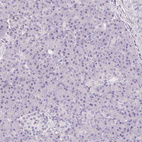

Immunohistochemistry analysis in human lymph node and skeletal muscle tissues using HPA050525 antibody. Corresponding CD69 RNA-seq data are presented for the same tissues.